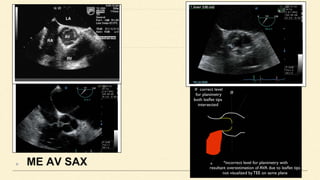

ME AV SAX

ME AV LAX

TG LAX & DEEP TG LAX